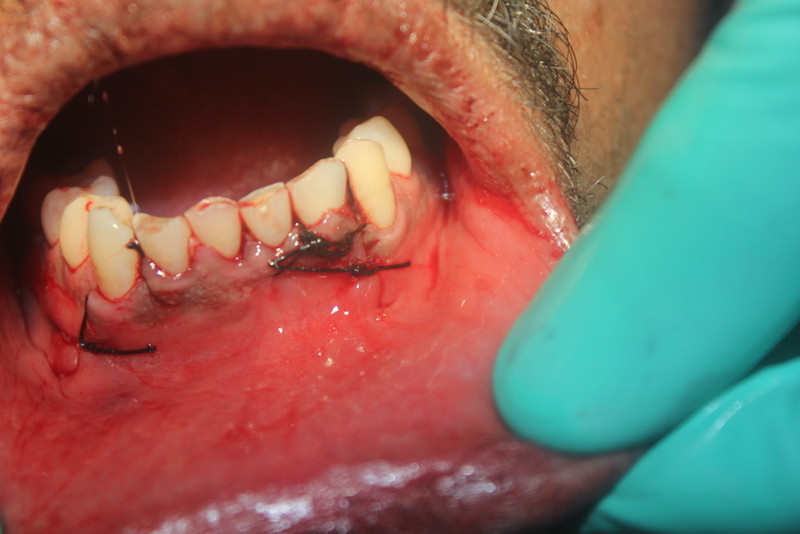

Apicoectomy